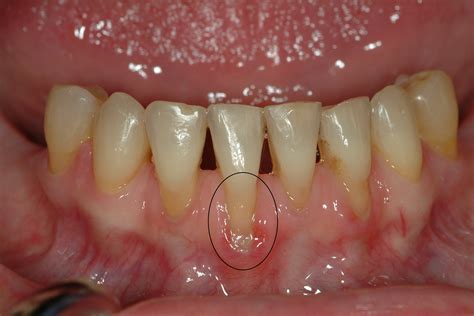

How To Reverse Gum Recession

It is not possible to reverse receding gums at home, but people can take steps to stop it from getting worse. Some ways to prevent gum recession include maintaining good oral hygiene, avoiding ...

One of the most common concerns patients bring to the dental chair is receding gums. Often, the immediate assumption is: "I must have gum disease." While this can be true, gum recession isn't always a ...

Gum graft surgery, also known as gingival grafting, is a surgical procedure that removes gum tissue from one area and places it in another. It’s often used to cover exposed tooth roots or correct gum ...